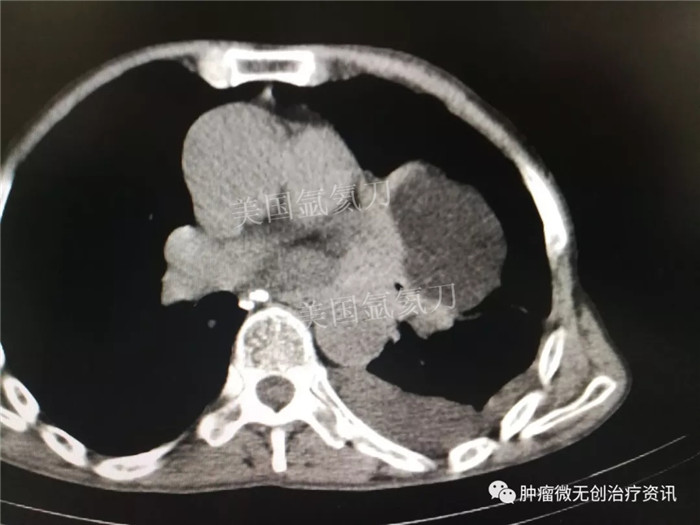

郑州大学附属郑州中心医院氩氦刀冷冻消融治疗肺部肿瘤

67岁老年男性患者,因肺部肿瘤,于7月28日行氩氦刀冷冻消融治疗。